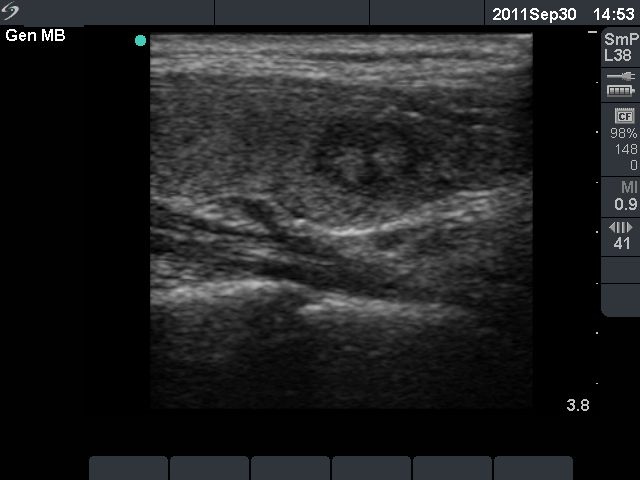

First examination (first row):

Clinical presentation: a 17-year-old girl who has been treated for hyperthyroidism for 2 years. She had no complaints.

Palpation: no abnormality.

Functional state: euthyroidism on daily 10 mg methimazole with TSH 2.14 mIU/L, FT4 13.2 pM/L.

Ultrasonography: the thyroid was echonormal with a hyperechogenic lesion in the central part of the right lobe. The vascularization was a little bit increased.Suggestion: discontinuation of thyrostatic therapy and follow-up examination 6 months later.